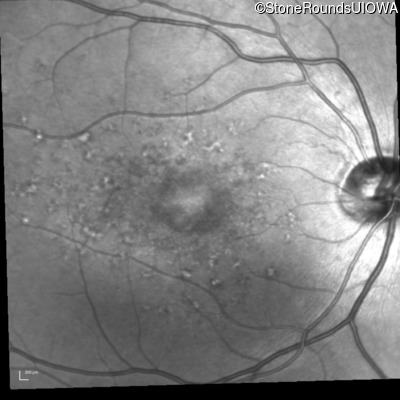

Fundus Photography - Right - 20/80 -1

Exemplar